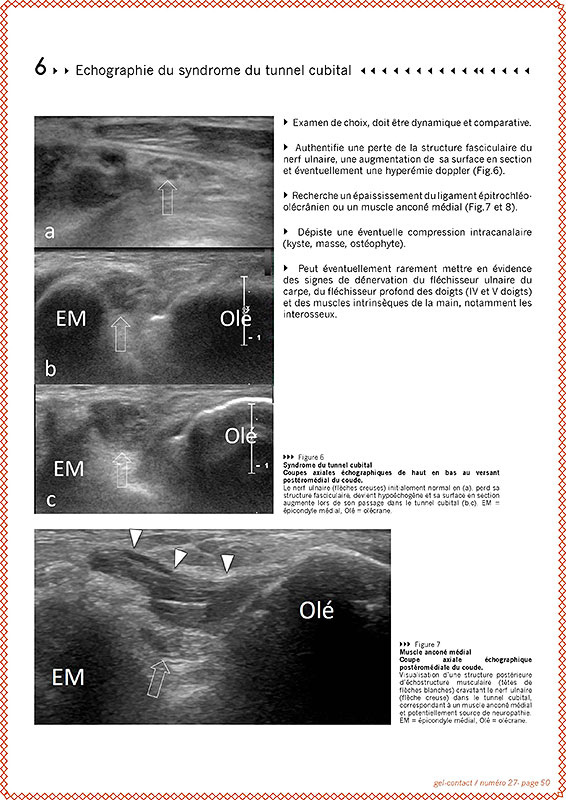

Gel Contact N°27

JUIN 2018